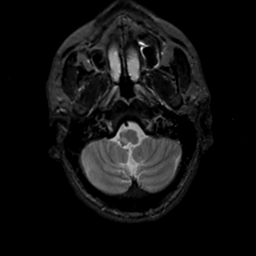

MR Study #7, March 24, 1991 -- Slice #6